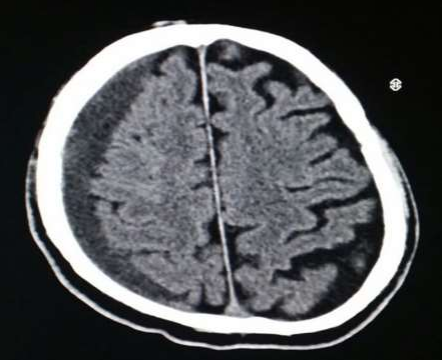

Fig 1,2,3,4,5,6,7,8,9,10,11,12,13,14,15

Figure 1

Figure 2

Figure 3

Figure 4

Figure 5

Figure 6

Figure 7

Figure 8

Figure 9

Figure 10

Figure 11

Figure 12

Figure 13

Figure 14

Figure 15